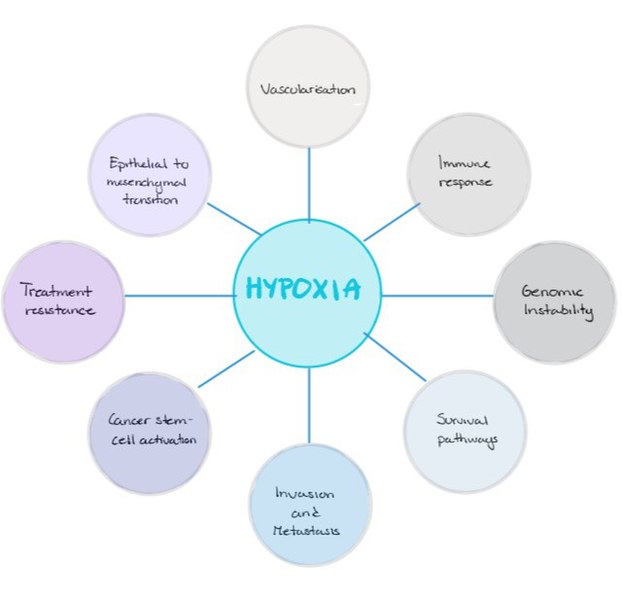

4 – Definitions: hypoxemia, hypercapnea, hypoxia, (an informative/summary figure can be made using Bio-render)

Hypoxia – is a condition involving abnormally low levels of oxygen in body tissues. It can lead to bluish skin, confusion, difficulty breathing, restlessness and fast heart rate. Hypoxia is different to hypoxemia as hypoxia is low oxygen levels in tissues whereas hypoxemia is low oxygen levels in blood.